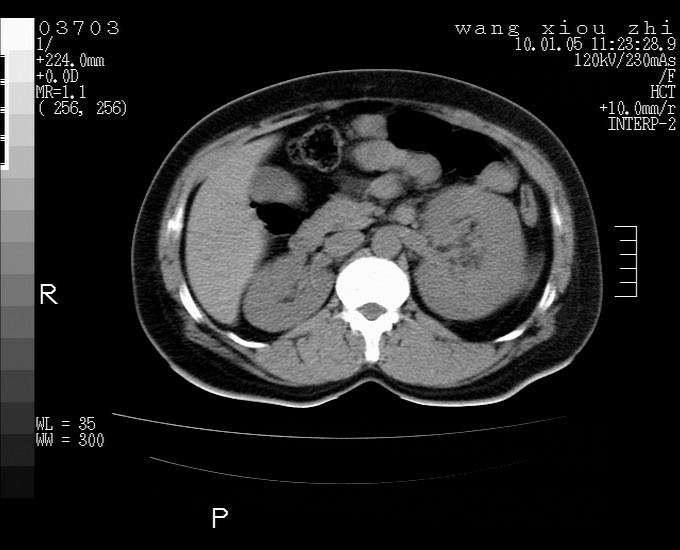

标题: CT23996:f,40.B超提示肿物。 [打印本页]

标题: CT23996:f,40.B超提示肿物。

左肾体积增大!下极见一密度略高团状软组织影!肾周结构组织未见明显异常!考虑左肾占位!建议增强!病史?

左肾占位,肾门及腹膜后淋巴结肿大,考虑透明细胞癌可能性大,建议增强

左肾体积增大,内见肿块影,考虑占位,建议增强。